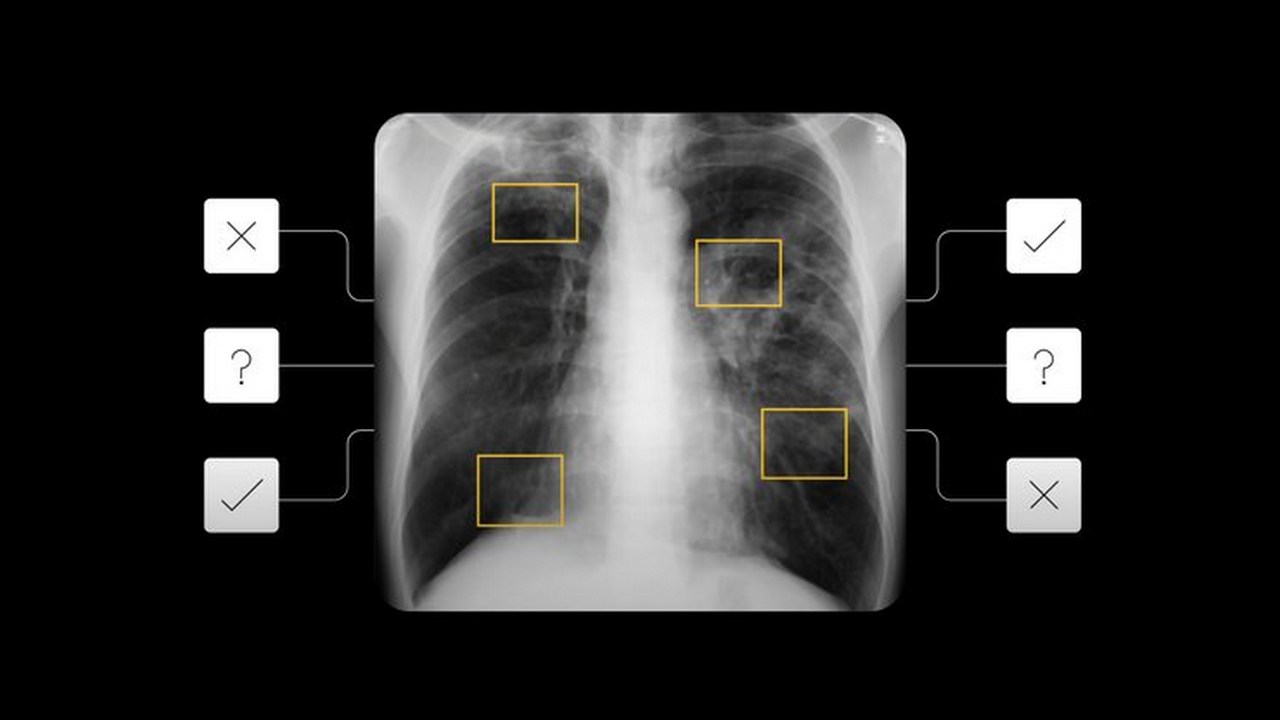

The deep learning system provides any number between 0 and 1, indicating the severity of tuberculosis in the patients. Image: Google[/caption] The previous research which detected nodules or fractures in chest X-rays or collapsed lungs was used to build the latest AI tool. In order to ensure that the AI tool is effective on a wide range of races, Google trained the model using de-identified data from nine countries. It was then tested on cases from five countries. In their study, the Google AI researchers have found that on the basis of the chest X-ray, the deep learning system can identify patients who are likely to have active TB. It provides any number between 0 and 1, indicating the severity of tuberculosis in the patients. Google’s AI tool was able to accurately detect the cases of TB. The blog also states that the detection rates of false-negative and false-positive cases were similar to 14 radiologists. One of the highlights of this latest AI tool is that it is able to maintain detection accuracy even while examining HIV patients. Generally, it is difficult to screen TB in HIV patients as their chest X-rays may differ from those of other TB patients. For the implementation of this AI tool, the tech giant says that there needs to be agreement on the risk level which makes a person eligible for additional testing. Also read: